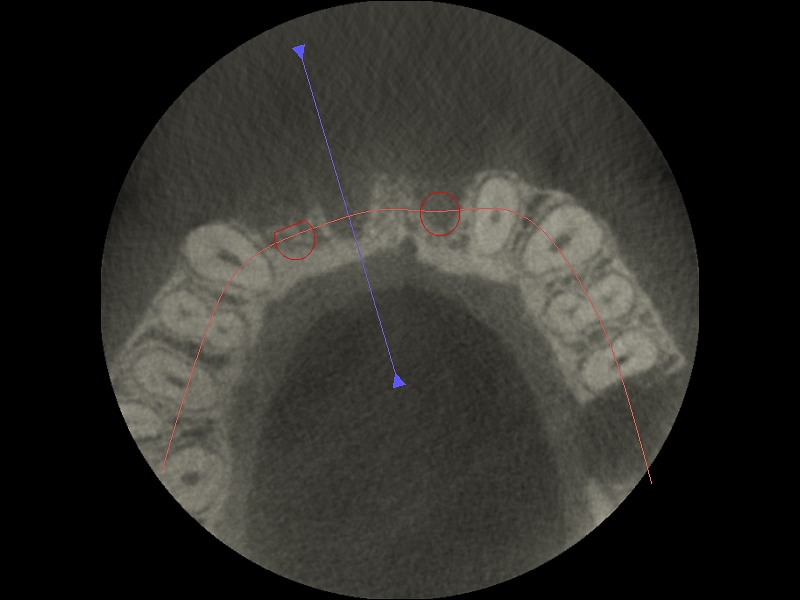

03/17 - Vestibular defect of hard tissue visible in CBCT examination with planned position of future implants

Block augmentation with maxgraft® block & mucoderm® - Dr. K. Chmielewski